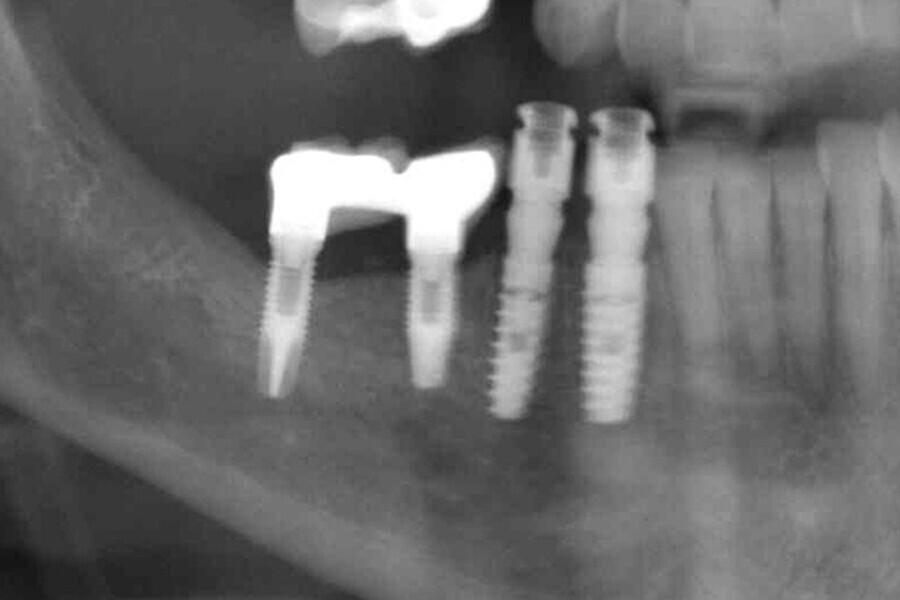

Figs. 9. Colocación de 2 implantes post-extracción en posiciones del 43 y 44 y control radiográfico post-extracción.

Figs. 10. Colocación de 2 implantes post-extracción en posiciones del 43 y 44 y control radiográfico post-extracción.